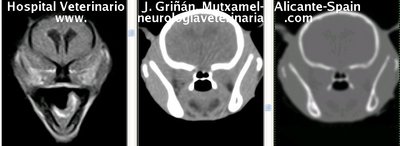

Se muestran cortes transversales de Resonancia Magnética (imagen a la izqda del lector), TC contrastado para tejidos blandos (imagen del centro) y TC contrastado para tejidos duros (imagen de la derecha del lector).

Nótese como la Resonancia supera al TC en el contraste de tejidos blandos (encéfalo y médula espinal) y en el de líquidos (ojo y líquido cefalorraquídeo), mientras que el TC supera a la resonancia en el contraste de tejidos duros (hueso) y aire (senos, cavidad nasal y bullas)

Cortes a nivel de los lóbulos cerebrales parietales